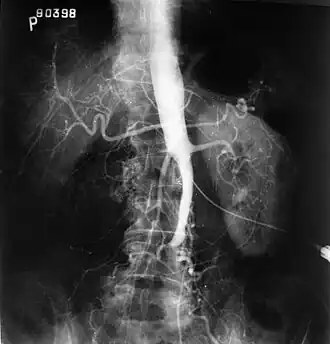

Imagem fluoroscópica de uma aorta afetada pela síndrome de Leriche

O exame físico geralmente mostra pulsos femorais enfraquecidos e um índice tornozelo-braquial reduzido. O diagnóstico pode ser verificado pela digitalização em duplex em cores, que revela uma taxa de velocidade sistólica de pico ≥2,5 no local da estenose e/ou uma forma de onda monofásica. A angiografia por ressonância magnética e a angiografia por tomografia computadorizada múltiplo detector são frequentemente usados para determinar a extensão e o tipo de obstrução. Outra técnica é a angiografia por subtração digital, que permite a verificação do diagnóstico e tratamento endovascular em uma única sessão.[1] A angiografia fornece informações importantes sobre a perfusão e perviedade das artérias distais (por exemplo, artéria femoral). A presença de artérias colaterais na região pélvica e na virilha é importante para manter o fluxo sanguíneo crucial e a viabilidade dos membros inferiores. No entanto, a angiografia deve ser usada apenas se os sintomas justificarem intervenção cirúrgica.